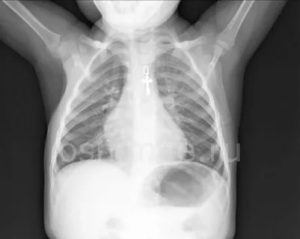

Диагностика пневмонии у детей с помощью рентгена вызывает ряд некоторых трудностей. Связано это с небольшим объемом легочной ткани и большим количеством структурных элементов на маленькую площадь, которая подлежит исследованию. Из-за этого появляется сложность в правильной оценке легочного рисунка, а также диагностирования состояния легочных корней и лимфоузлов.

Самым распространенным признаком пневмонии у детей, которые проявляются на снимках, являются очаговые тени в нижних сегментах легких диаметром 1-2 мм.

Пневмония на рентгенограмме у пациентов детского возраста не имеет выраженных отличий от взрослых, патология также характеризуется очагами просветления и затемнения. У детей в воспалительный процесс вовлекаются нижние отделы лёгких.

Рентгенография показывает следующее:

- очаговые затемнения диаметром 1-2 мм;

- увеличение внутригрудных лимфоузлов;

- деформация и усиление лёгочно-сосудистого рисунка;

- повышенная плотность затемнения (запущенная патология);

- в области патологического очага изменяется структура и размер лёгочного корня.

Рентгенодиагностика пневмоний у детей имеет некоторые затруднения в постановке диагноза. Обусловлено это меньшим объемом легочной ткани, большим количеством легочного рисунка, нежели у взрослого и вздутием тканей легкого. Для своевременной диагностики пневмонии важно оценивать клиническую картину заболевания.

Признаками и симптомами пневмонии у детей являются:

- небольшие затемнения нижних отделов легких;

- увеличение лимфатических узлов;

- деформация рисунка до 7 дней после избавления от патологических тканей.